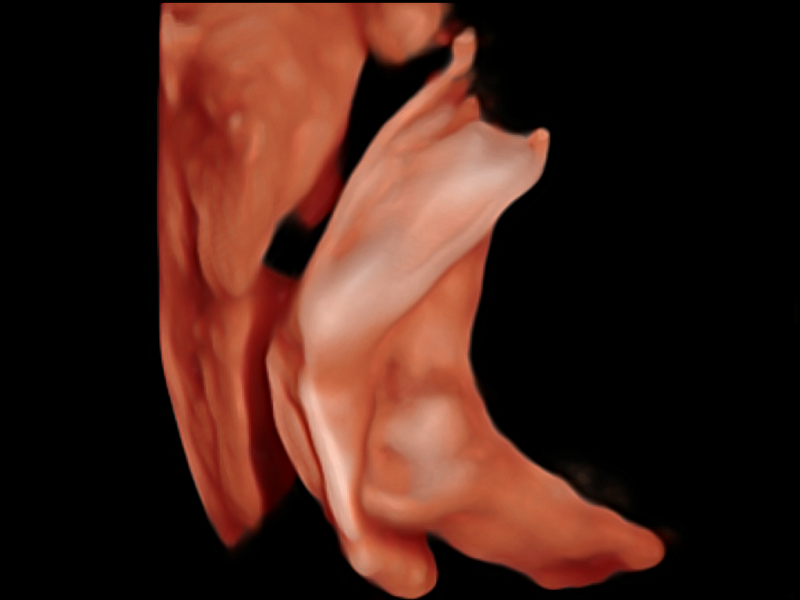

凸陣、線陣和相控陣探頭進行實時掃描時,開啟擴展成像模式,可以擴展超聲圖像視野,以便更完整地查看大的病灶或組織器官的解剖結(jié)構(gòu)。

通過色彩血流和實時寬景相結(jié)合,可觀察到完整的靜脈或動脈的血流,方便醫(yī)生檢查。實時掃查過程中,如有任何操作失誤也可以很容易地進行回掃擦除,而不會中斷掃查。